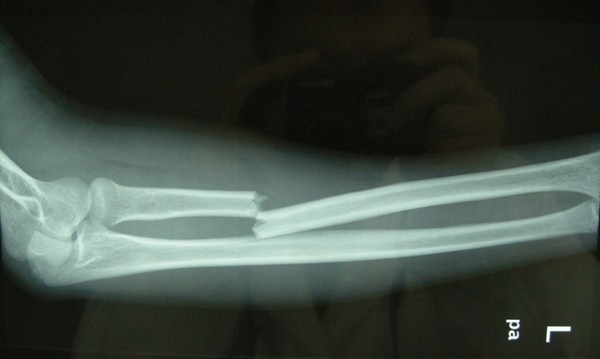

骨折后,為何遲遲不做手術(shù)呢?

今日,三院骨科專家一一為病人解開疑惑,很多骨折病人需要進行切開復位內(nèi)固定手術(shù)。但是,骨折通常伴有局部腫脹,這種開放性手術(shù)的時機,要根據(jù)骨折部位的腫脹程度來確定。有部分病人不理解手術(shù)和消腫之間的關(guān)系,很容易對醫(yī)生產(chǎn)生誤解。

如果病人骨折處腫得很厲害,一般要先消腫。否則,若強行進行內(nèi)固定手術(shù),容易并發(fā)感染。

不同的骨折部位,情況也是不一樣的。例如:肌肉豐富的大腿部位,較輕的腫脹也可以做手術(shù),這是因為該處肌肉比較豐富,做完手術(shù)之后軟組織可以覆蓋手術(shù)切口。然而,像小腿的脛骨、足部的跟骨等部位,軟組織較少,屬于皮包骨,倘若腫脹很嚴重時使用鋼板進行內(nèi)固定,手術(shù)以后將會出現(xiàn)軟組織覆蓋不了,皮膚也縫不上的狀況。所以,這些情況必須先消腫再手術(shù)。

隨著相關(guān)知識的普及,病人也漸漸能理解,腫脹嚴重卻強行手術(shù),將會導致皮膚感染、皮膚缺損、鋼板外露和骨髓炎等危害。